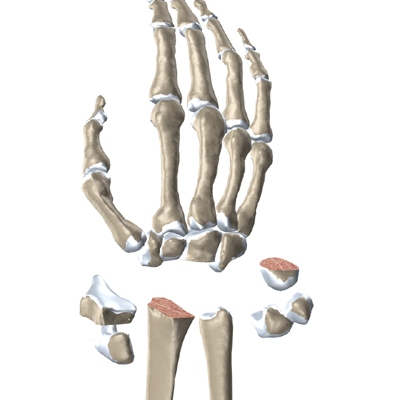

The surgeon needs to make room for the artificial joint. To do this, most of the first row of:

Carpal Bones are Removed

from the wrist. The end of the radius is also shaped to fit the prosthesis.